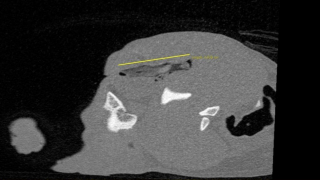

Juste avant les soins, les vétérinaires avaient réalisé un scanner au niveau de l’œil du chien pour mieux se rendre compte de la blessure. Après le scanner, ils se sont aperçus que le bâton était encore en un seul morceau et qu’il était logé juste au-dessus de l’œil de Mia. C’est une véritable chance pour la petite chienne : le bâton est ainsi plus facile à retirer pour les vétérinaires. Ces derniers parviennent à le faire sortir sans encombre.